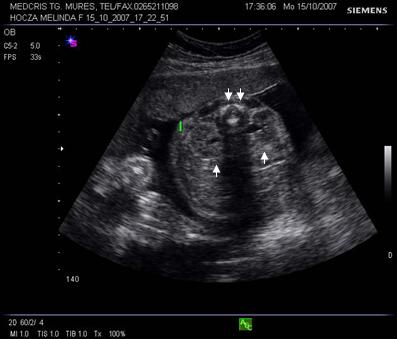

Fig. nr. 189. Sectiune transversala fetala lombara cu evidentierea celor doi rinichi ( cate o sageata la nivelul pelvisului renal ). Se remarca arcurile vertebrale osificate ( doua sageti )